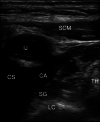

Figure 3. Right stellate ganglion block

Ultrasound view of percutaneous blockade of the right stellate ganglion. Bilateral blocks were performed during the resuscitation. The C6 vertebral body likely lies deep (below) the visualized region on this ultrasound image frame. The injection is targeted slightly medial to lateral, beneath the carotid artery, and then lidocaine is injected to visualize the separation of the muscular and fascial layers to confirm correct placement. A bilateral blockade was performed. SCM - sternocleidomastoid muscle, IJ - internal jugular vein, CS - clavicular shadow, CA - carotid artery, SG - stellate ganglion, TH - thyroid tissue, LC - longus colli muscle.